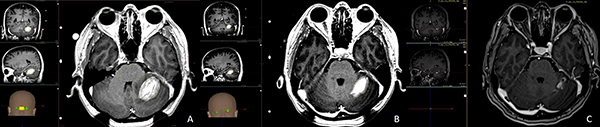

Los tratamientos con Infini™ fueron administrados a 28 (76%) pacientes, 19 (67%) de ellos en una sola fracción y 9 (32%) de ellos en protocolo de radiocirugía adaptativa, la dosis de prescripción para todo el grupo fue de 13.8 Gy (7.5-18Gy) a la curva del 50%, con dosis media en el PTV de 17.9 Gy (13.2-23.3Gy), con un volumen medio de 16.3 cc (8.5-78.4 cc). Para el protocolo de radiocirugía de dos sesiones la dosis de prescripción fue de 14.5 Gy (10-18) con una dosis media de 20.5 Gy (13.2-23-3) en la primera sesión a un volumen de 12.8 cc (8.5-78.4) y de 13.5 Gy (10-18) con una dosis media de 18.6 Gy (13-26) en la segunda sesión a los 30 días a un volumen de 4.3 cc (0.4-70) por efecto del tratamiento inicial y la consecuente reducción del tamaño tumoral (figs. 1 y 2).

A) Metástasis frontal izquierda de cáncer de mama con receptores hormonales negativos que produce efecto de masa midiendo en la primera sesión de radiocirugía 37 cc en su volumen inicial, la dosis de prescripción es 12 Gy a la curva del 50% señalizada en verde, la sombra anaranjada representa todo el volumen interno que está recibiendo más de 15 Gy. B) Imágenes durante el segundo tratamiento a los 30 días, el volumen de la lesión se ha reducido 62% (vol. 14cc) la nueva dosis de prescripción es 12 Gy a la curva del 50% señalizada en verde, la sombra anaranjada representa todo el volumen interno que está recibiendo más de 15 Gy. C) Control a los 3 meses, el efecto de masa ha sido resuelto por completo.